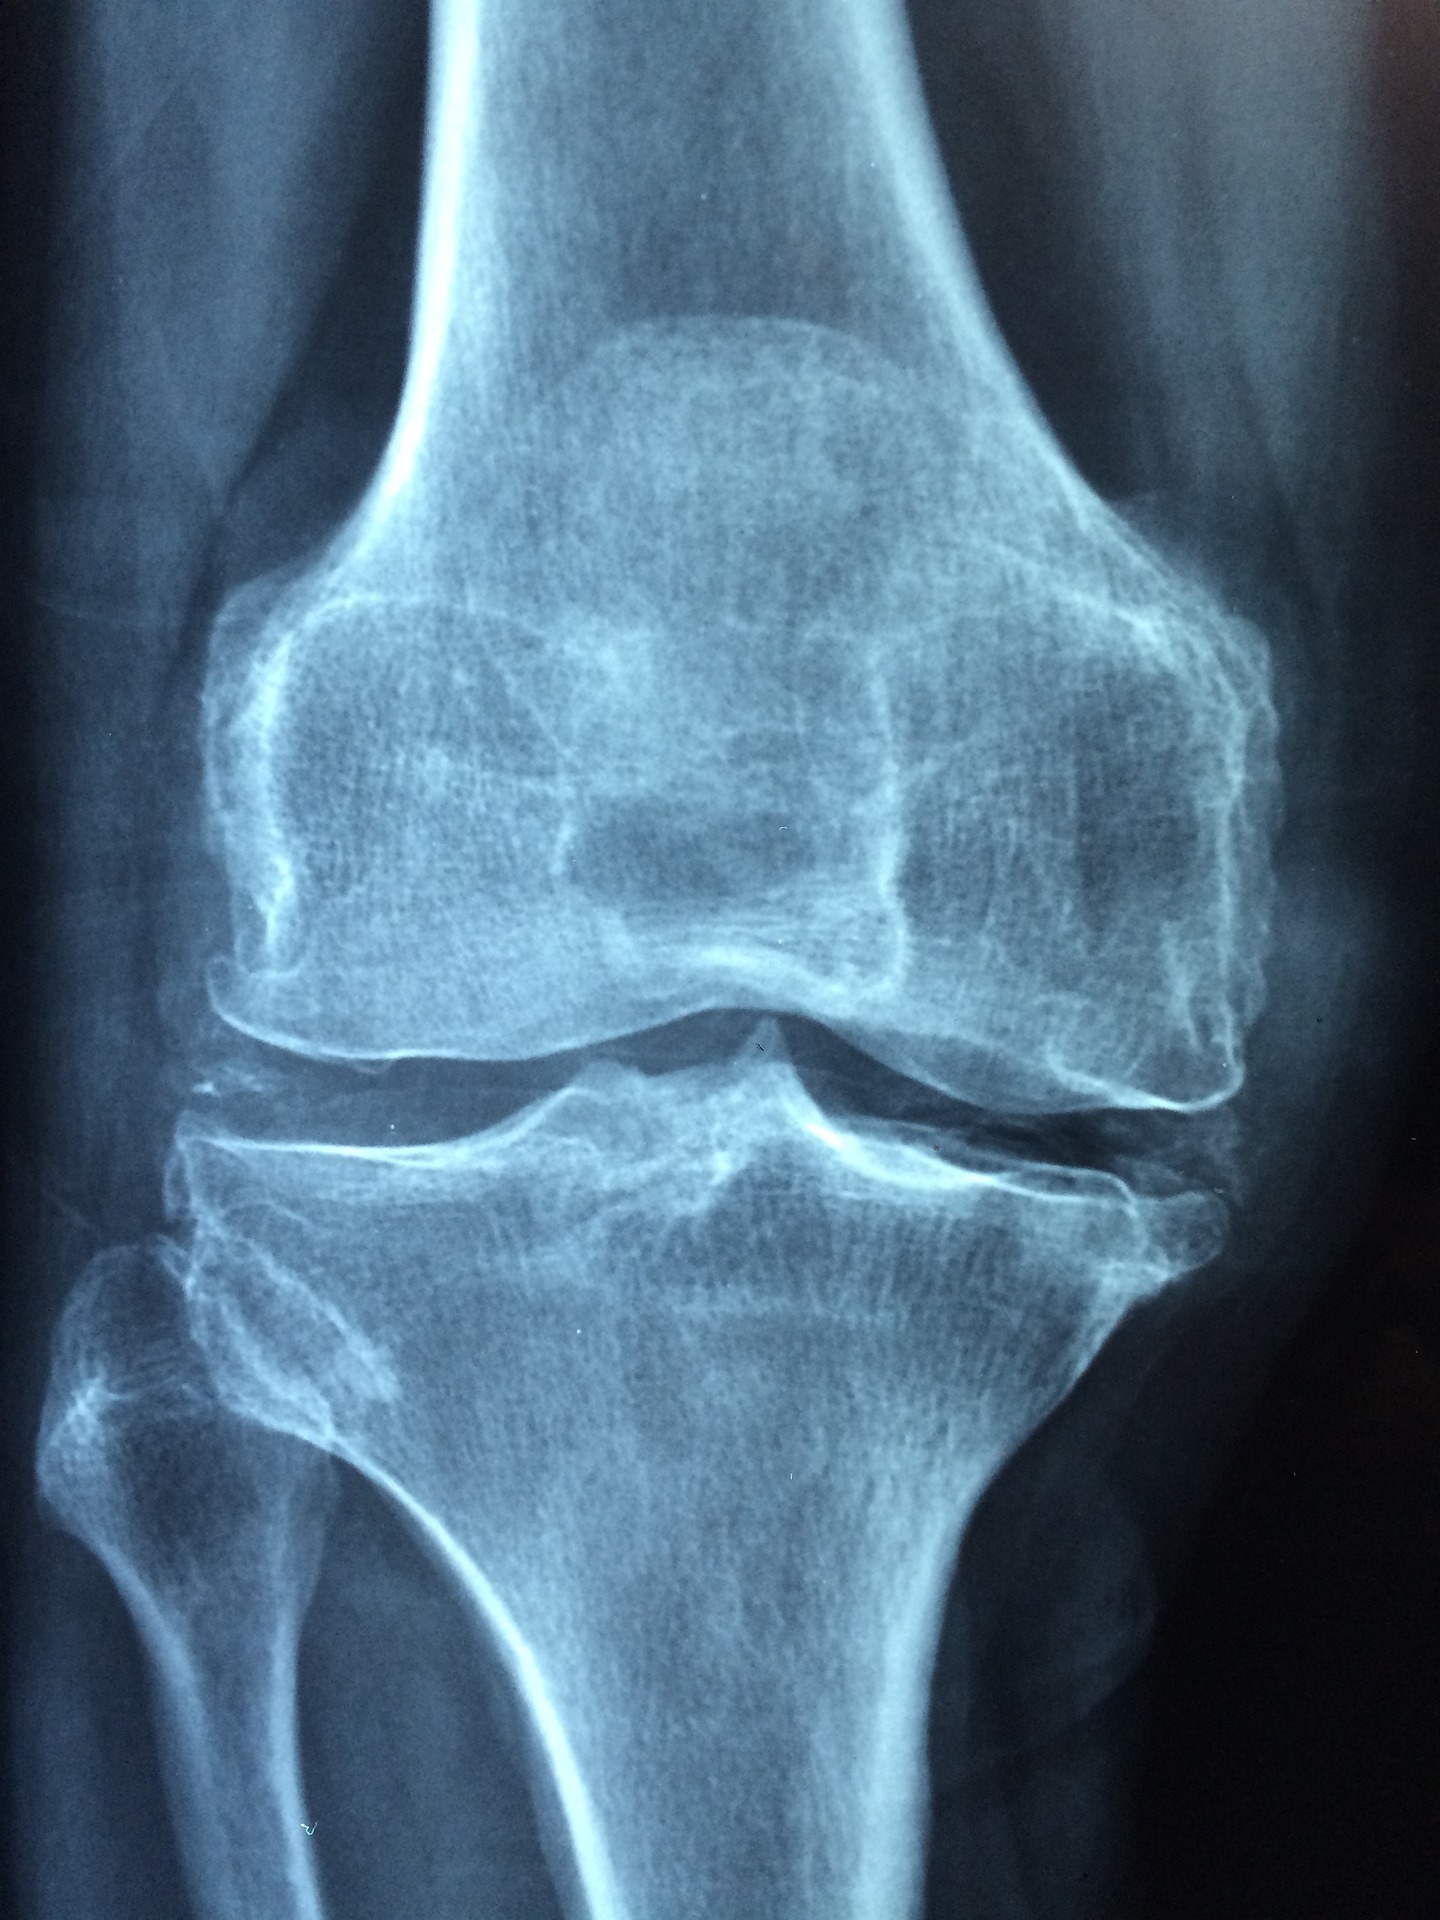

1. 무릎 관절염 통증, 냉찜질하기와 다리를 심장보다 높게 두기

무릎 관절염이 있다면 팔다리를 움직일 때마다 아프고, 관절이 붓거나 뜨거워집니다. 이는 뼈와 뼈 사이에 있는 연골, 관절낭, 활막, 인대, 힘줄 등에 염증이 생기기 때문입니다.

밤에 관절염 통증이 심한 이유는 관절에 염증이 생기면 몸을 움직일 때마다 피로가 쌓여 통증이 생기기 때문입니다. 낮에는 평소 일상생활에 집중하느라 그 통증을 인식하지 못하지만, 밤에는 온 신경이 통증에 집중되어 더 아프게 느껴집니다. 밤에는 다리를 지나는 혈류가 증가해 관절이 자극을 더 많이 받아서 통증이 심해지는 것으로 연구결과가 있습니다.

이럴 땐 무릎을 냉찜질해서 부기를 완화하면 통증이 조금이라도 줄어듭니다. 또한 베개나 쿠션을 다리 아래에 놓아 다리를 심장 위치보다 높게 두는 것도 도움이 됩니다. 그렇게 하면 다리 쪽에 흐르는 혈류량이 줄어들어 통증이 덜해지기 때문입니다. 통증이 너무 심하다면 자기 전에 진통소염제를 먹어 새벽 동안 약효가 나타나게 하는 방법도 있지만, 이렇게 약을 먹을 경우 반드시 의사와 상의해야 합니다.